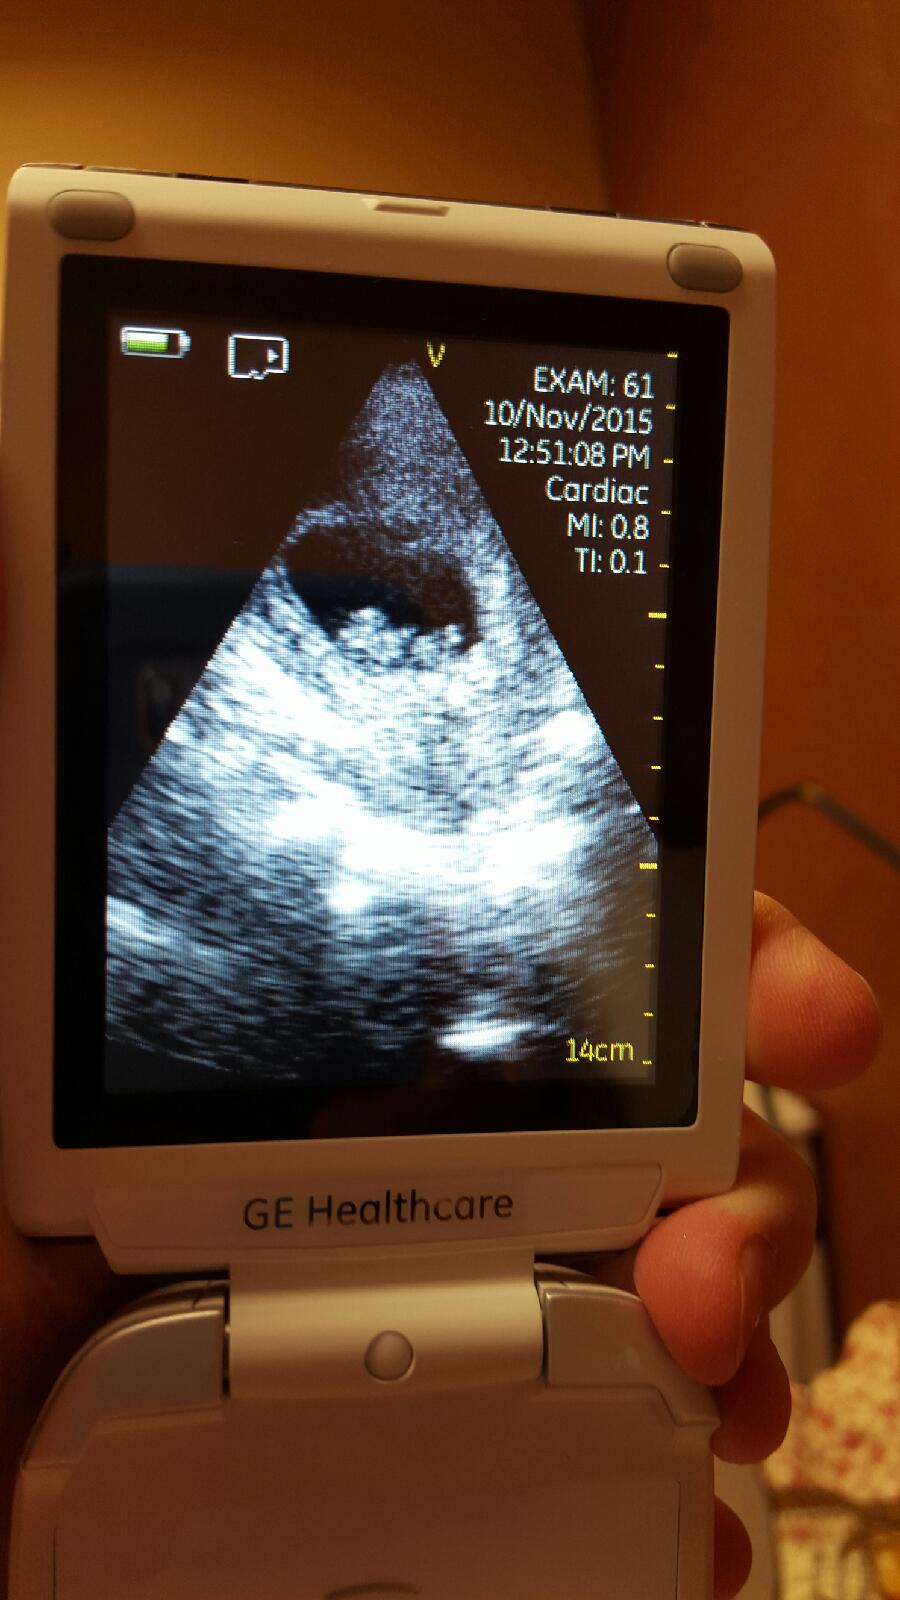

I just got out of my apt. The doctor literally found it immediately after putting it on my skin. Like without even moving it around. 172bpm. Lol I feel like an idiot. But I'm over the moon happy. Baby is just fine